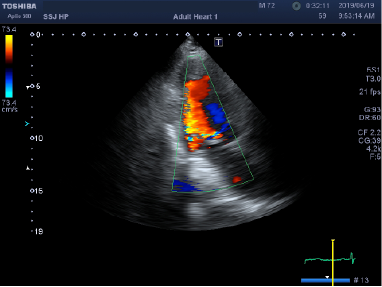

心臓弁膜症

心臓は左心房、左心室、右心房、右心室という四つの部屋に分かれています。血液が正しい方向にだけ送り出されるように、それぞれの部屋の間には逆流防止弁がついています。 これらの弁の開きや閉じが悪くなって心臓に負担がかかるようになり、最終的に心不全に至る病気が心臓弁膜症です。 心臓弁膜症の中でも大動脈弁狭窄症は、高齢者に多くみられる弁膜症であり、今後も増加が予想されています。心臓弁膜症の診断にもっとも重要な検査は心エコー検査です。

当院では、初診の患者さんには丁寧な聴診とともに心エコー検査を施行し、弁膜症を見逃さないようにしています。弁そのものを治す薬はありませんので、重症の場合には適切なタイミングで手術を考慮する必要があります。

弁膜症が軽症~中等症の場合には、心エコー検査で定期的に心臓の機能をチェックしていきます。中等症~重症で、治療を要すると考えられる場合には精査を行い、心臓外科の手術ができる病院へ紹介しています。

心臓弁膜症の心エコー画像